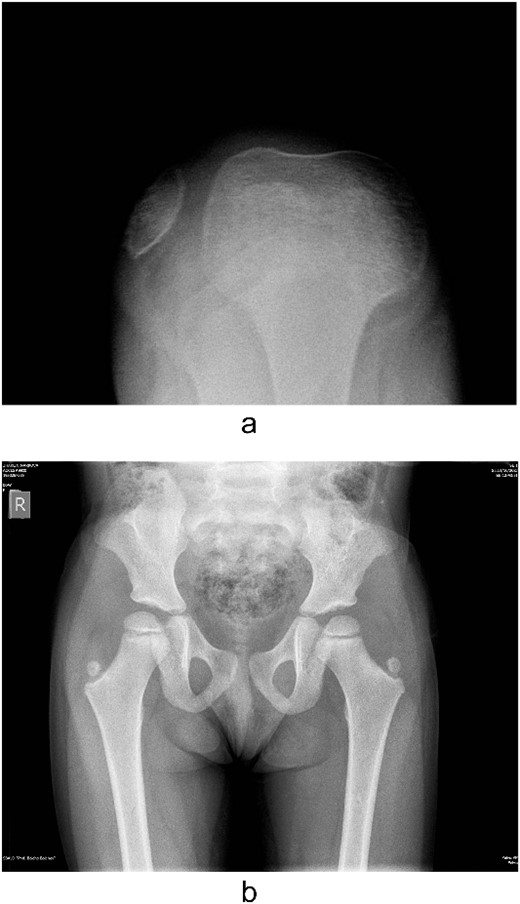

Examination of the right and left upper limbs revealed slightly underdeveloped arm muscles, but no deficiency in motor function was noticed, neither radial head dislocation. Lateral dislocation of the patella with every flexion and relocation, with extension, was observed. Normal range of motion was discovered for the left knee; the patella was hypoplastic and had unstable kinematics (Fig. 2). No pain was elicited with patellar movements, and the knees were otherwise stable. Severe spine deformity was not present except for slightly distinguishable lordosis. Examination of the abdomen, central nervous system (CNS), and fundus was normal.

Several radiographs were taken, showing the pathognomonic bilateral iliac horns [3], normal-shaped, without signs of hypoplasia, radio-humeral joint. Both patellae were hypoplastic, with complete lateral dislocation of the right patella, as distinguished in the skyline Merchant view (Fig. 4).